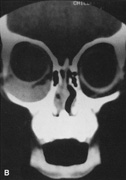

Fig. 14. A,B. Large intraorbital lymphangioma causing proptosis and optic nerve compression in a 2-year-old child. C. View of the left orbit from above after removal of the frontal bone flap, including the supraorbital rim and orbital roof. An extensive exposure of the entire superior and lateral orbit is afforded. The levator and superior rectus complex is being retracted laterally with a muscle hook, whereas the Freer elevator retracts the superior oblique muscle medially. The frontal nerve can be seen running from posterior to anterior over the superior orbit. The orbital mass is exposed in this fashion. D. The fronto-orbital bone flap is wired back in place after completion of the procedure. E. Postoperative appearance of the patient. F. The postoperative CT scan shows complete removal of the lymphangioma. This large and diffuse lesion would have been difficult to remove with any other approach.

A burr hole is placed in the midline just above the orbital rim. This burr hole usually enters the frontal sinus. A second burr hole is placed anteriorly in the temporalis fossa at the junction of the cranium and orbit so that both compartments are exposed. Two or three additional holes are made in the frontal bone connecting the first two holes. The orbital rim is cut from the midline inferiorly, and the lateral orbital rim is cut from the temporalis fossa anteriorly. The dura is freed from the undersurface of the bone flap and is elevated superiorly, and the orbital roof is cracked off. The frontal bone, orbital roof, and supraorbital rim break off in one piece. The brain is retracted superiorly, and the remaining orbital roof is removed with bone rongeurs (see Fig. 14C).

After removal of the bony roof, the periorbita is visible. Typically, the periorbita is thin, and the levator rectus muscle and frontal nerve are visible beneath it. If exposure of the posterior optic nerve is desired, the dura can be elevated over the optic canal. The canal can be unroofed to decompress or explore the optic nerve, and the dura may be opened to view the intracranial optic nerve and the chiasm. At the orbital apex, the annulus may be cut to allow more anterior dissection and removal of the optic nerve in cases such as optic nerve glioma or meningioma. Because the superior orbital fissure and its contents lie lateral to the nerve, the intraconal space is entered on the medial side of the optic nerve. The orbital dissection can be carried out with a minimal amount of brain retraction after the en bloc removal of the frontal bone, supraorbital rim, and orbital roof.

After the dissection, the dura is closed and the frontal bone flap is plated or wired back into position (see Fig. 14D). The orbital roof is functionally restored with the replacement of the bone flap. The sinuses must be sealed off with muscle, pericranium, or other tissue. The coronal flap is closed in layers. The postoperative appearance is unchanged because the bone flap is replaced in one piece. Problems with globe ptosis, enophthalmos, pulsatile proptosis, or meningitis are rare. However, extensive mobilization of the temporalis may result in cosmetically significant temporal atrophy. Orbital apical dissection often results in extraocular motility dysfunction as a result of traction on the third, fourth, or sixth cranial nerves, but cranial nerve function usually recovers unless the nerves have been transected.